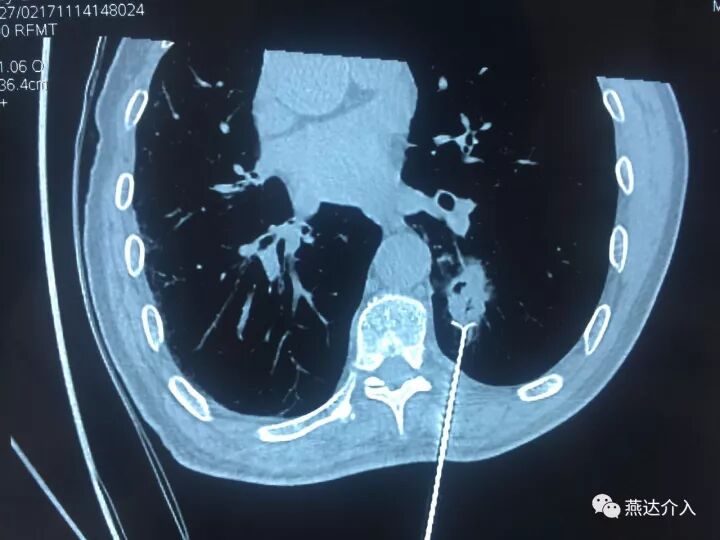

近日燕达医院收治一名肺内占位患者,行PET-CT考虑肺内占位,恶性可能,肺部多发小结节,考虑转移。为进一步明确肺内占位性质,放射介入科予患者穿刺活检,病理证实为肺鳞癌。为治疗肿瘤,决定予患者行肺癌射频消融术。

术中予患者2cm射频针3针消融,术后可见病灶周围晕征出现,肿瘤内可见消融后气化影,消融效果全面完全,术后患者情况良好,无不适。